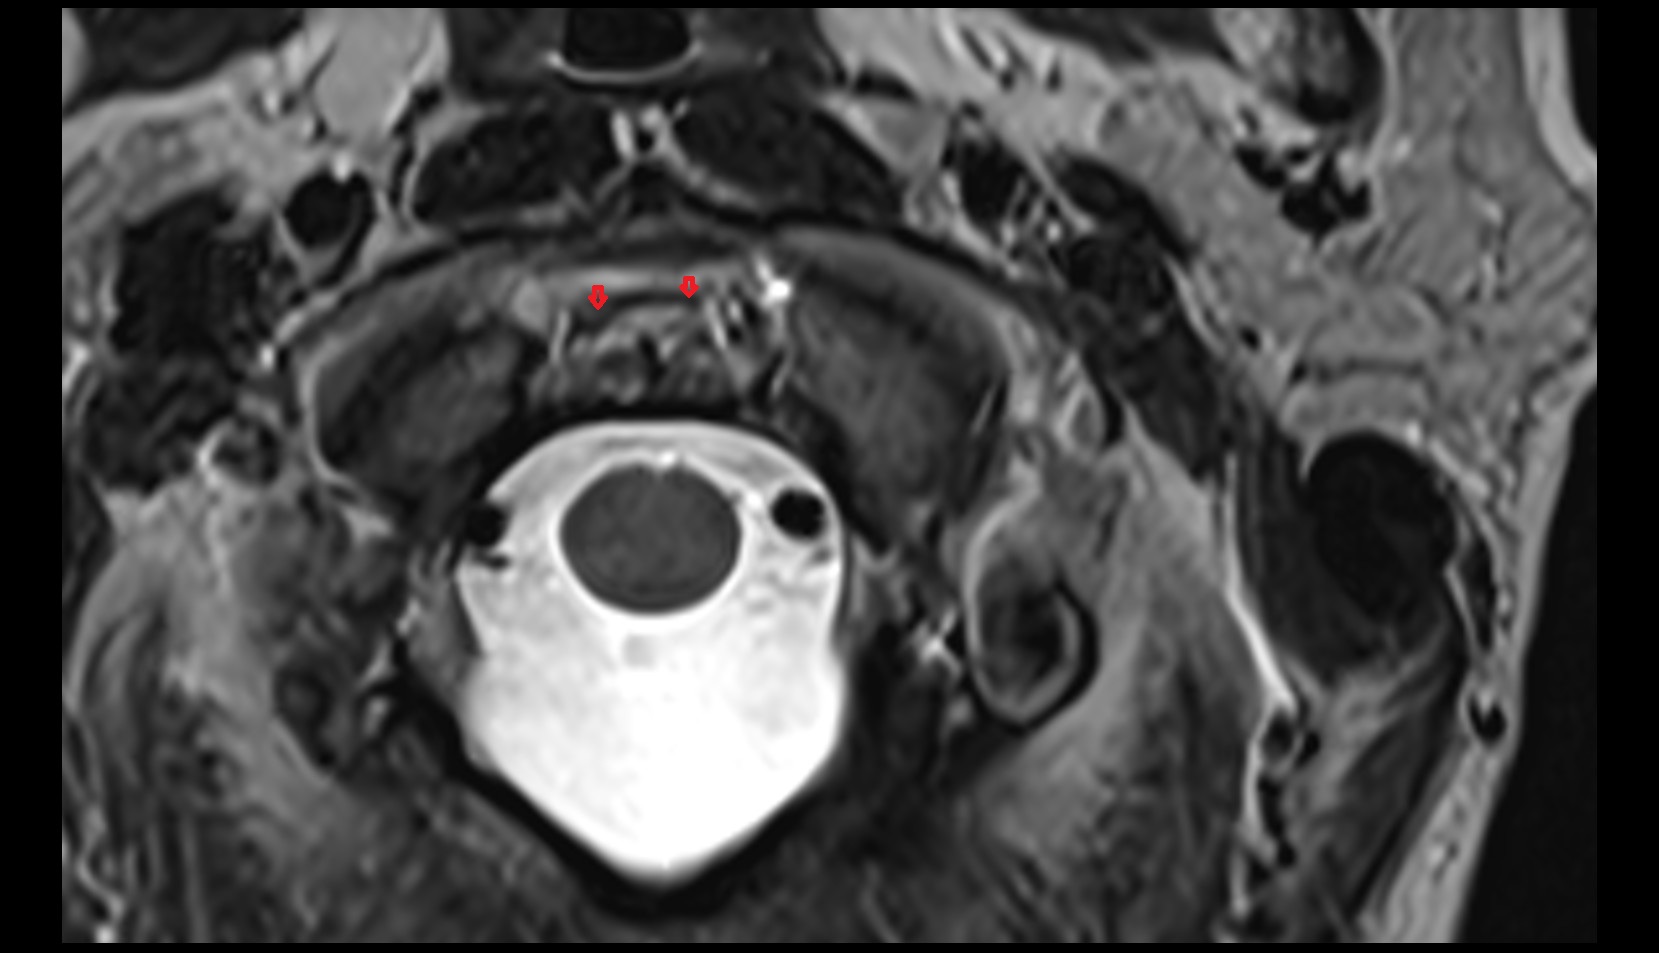

- Spinal cord

- Upper cervical spinal cord

- subarachnoid space of spinal cord